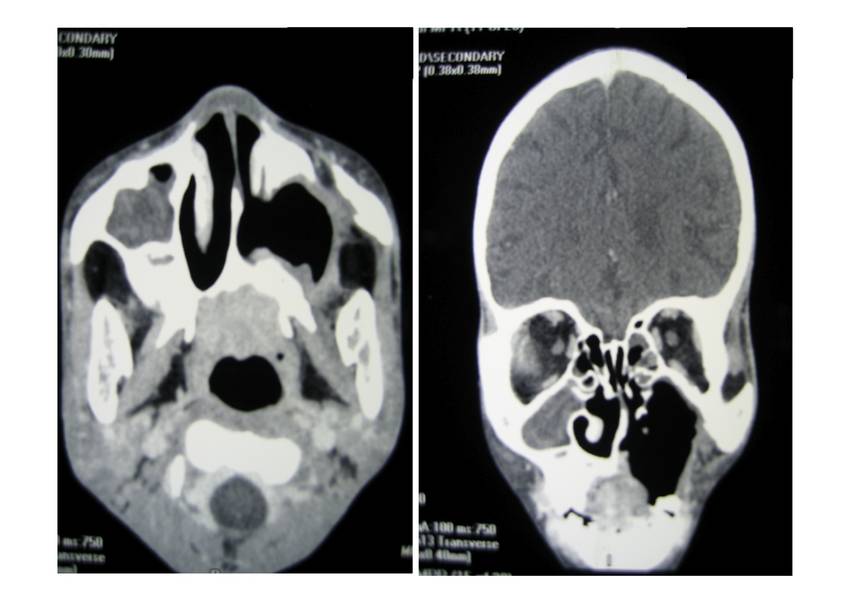

CT Scan of Face and Brain

Shows destruction of the left maxilla